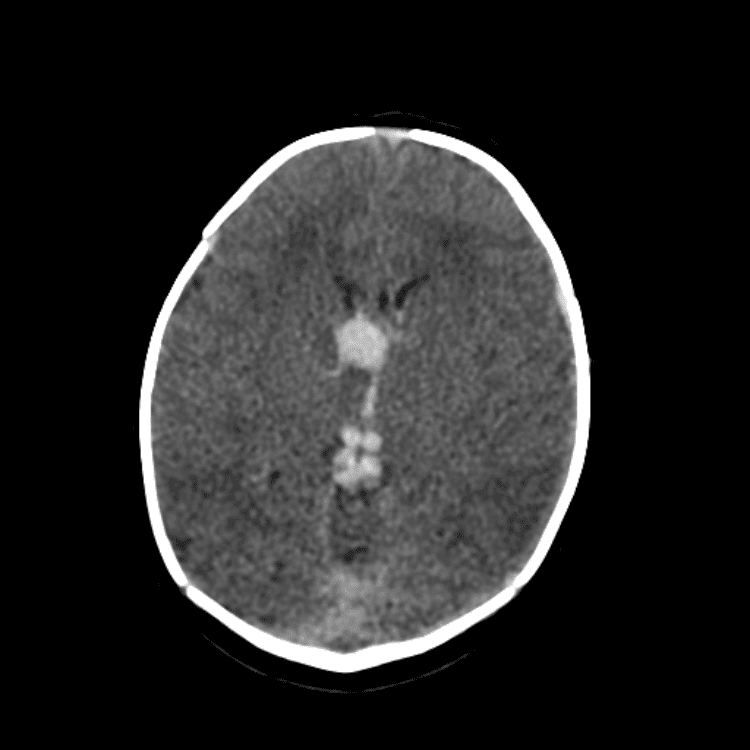

Nontraumatic Brain

Classic